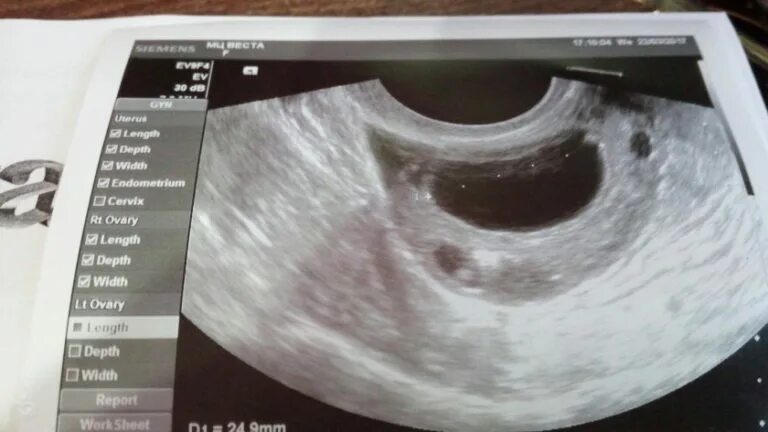

Когда делать узи после месячных